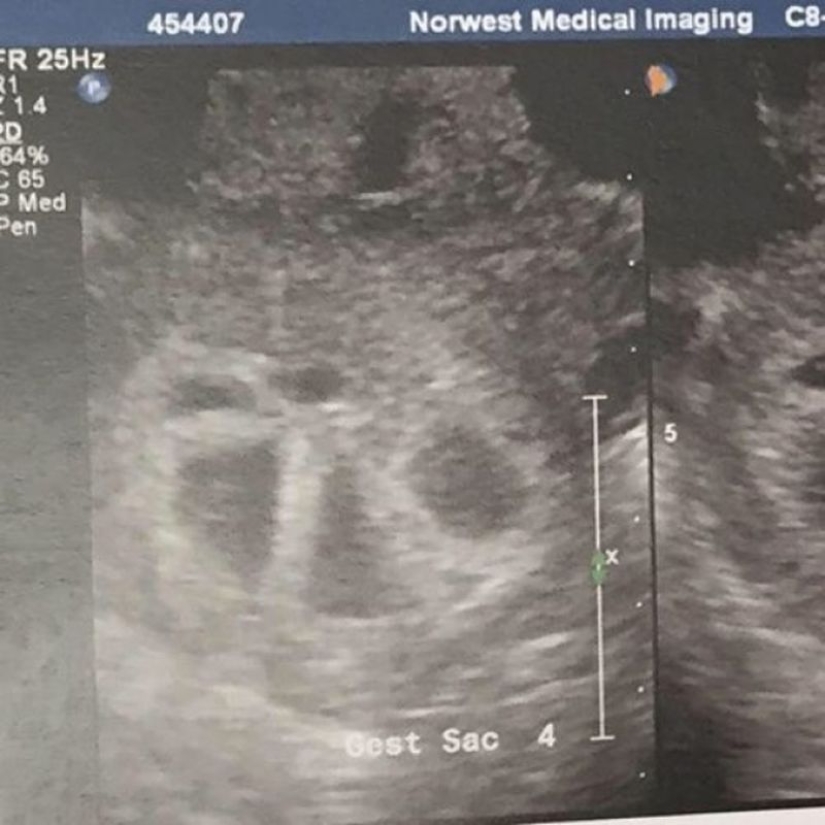

2. "Durante la primera ecografía, el médico comenzó a contar los óvulos fetales:" ¡El primero, el segundo, el tercero, el cuarto, el quinto!"", dice Kimberly. "¿Oí bien? Hay CINCO de ellos??? Pregunté. Y luego perdí el poder del habla y solo pude reír."(Por cierto, la probabilidad de concebir quintillizos de forma natural es de 1 en 55 millones).